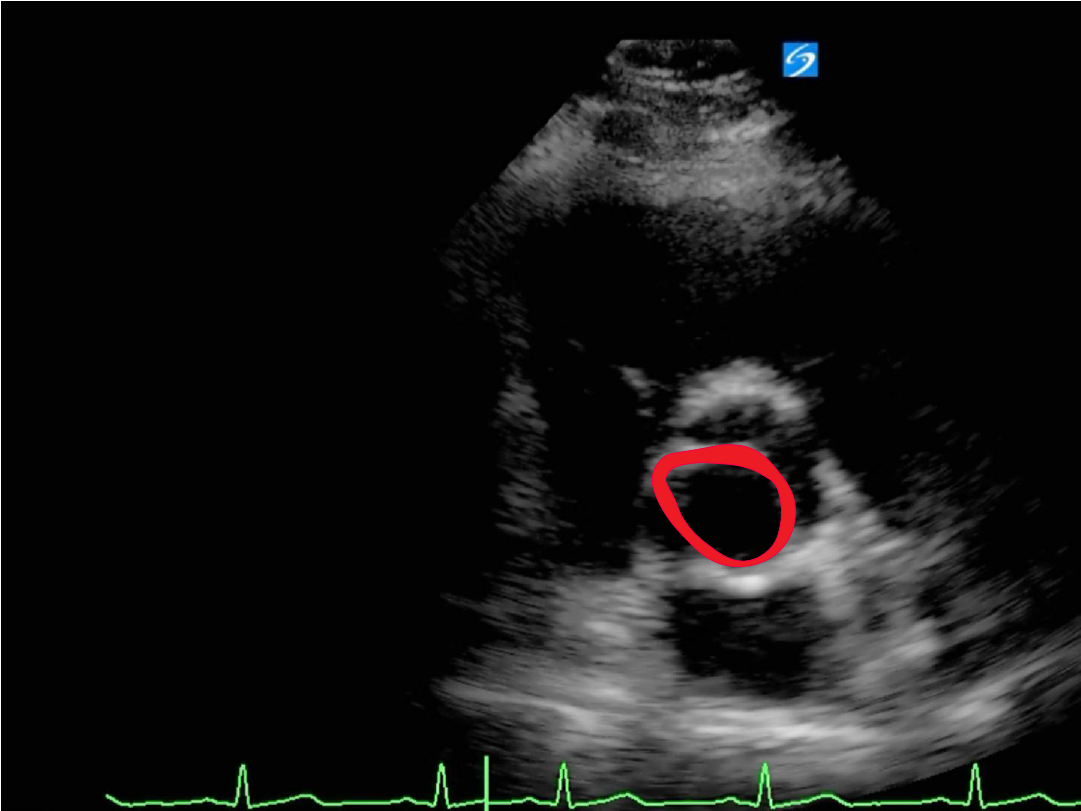

From www.criticalcare-sonography.com

Bicuspid Aortic valve Critical Care Sonography Is The Bicuspid Valve Open Or Closed When The Left Atrium Contracts  It is also known as the bicuspid valve because it contains two. The mitral valve is on the left side of the heart and allows the blood to flow from the left atrium into the left ventricle. Between the left atrium and left ventricle c. Between the right atrium and right ventricle b. The bicuspid valve is open when left. Is The Bicuspid Valve Open Or Closed When The Left Atrium Contracts.